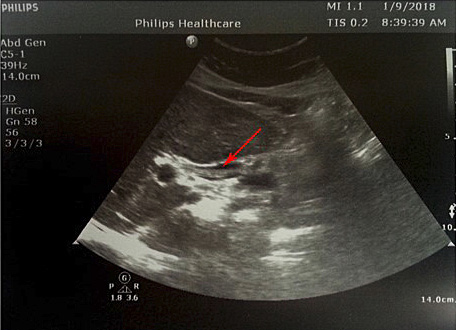

2 pav. Prisipildymo defektas (helmintas) BTL (pažymėta rodykle), nesant echogeninio šešėlio

Atlikus ultragarsinį pilvo tyrimą, konstatuota, kad tulžies pūslė pašalinta, BTL 0,8–1,0 cm pločio. Jo spindyje pastebėtos hiperechogeniškos masės (0,6–0,8 cm skersmens), distaliniame gale susiliejančios į didesnes sankaupas (1, 2 pav.). Kitų vidaus organų ir struktūrų matomų patologinių pokyčių nenustatyta.

Sergant tulžies latakų askaridoze, kraujo tyrimai gali atitikti normos ribas. Tokiu atveju įtarti patologiją padeda paciento nusiskundimai, išsami ligos ir gyvenimo anamnezė (kelionės, namų aplinka, valgymo įpročiai ir sąlytis su dirvožemiu). Specifinių (ligą diagnozuojančių) laboratorinių tyrimų askaridozei nustatyti nėra. Tiksliai diagnozuoti parazitų invaziją į žarnyną, kai laboratoriniai tyrimai nepatologiniai, galima identifikavus askaridžių kiaušinėlius paciento išmatose [3, 27]. Kirmėlių migraciją į tulžies latakus galima nustatyti atlikus ultragarsinį tyrimą. Dažnai ultragarsu pastebimas prisipildymo defektas BTL. Jis būna pailgos arba cirkuliarios formos, be tulžies latakų akmenims būdingo šešėlio – artefakto. Dėl šios priežasties ultragarsu stebimas prisipildymo defektas dar vadinamas „minkštu“ radiniu (1, 2 pav.). Nors ultragarsinis tyrimas vertinamas kaip jautrus ir specifiškas (atitinkamai 40–70 proc. ir 90 proc.), tyrimo kokybė priklauso ir nuo tyrėjo patirties. Tulžies latakuose esant oro po buvusių intervencijų arba kirmėlių maceracijos metu, kai kirmėlė negyva, ji gali būti nepastebėta [2, 3].